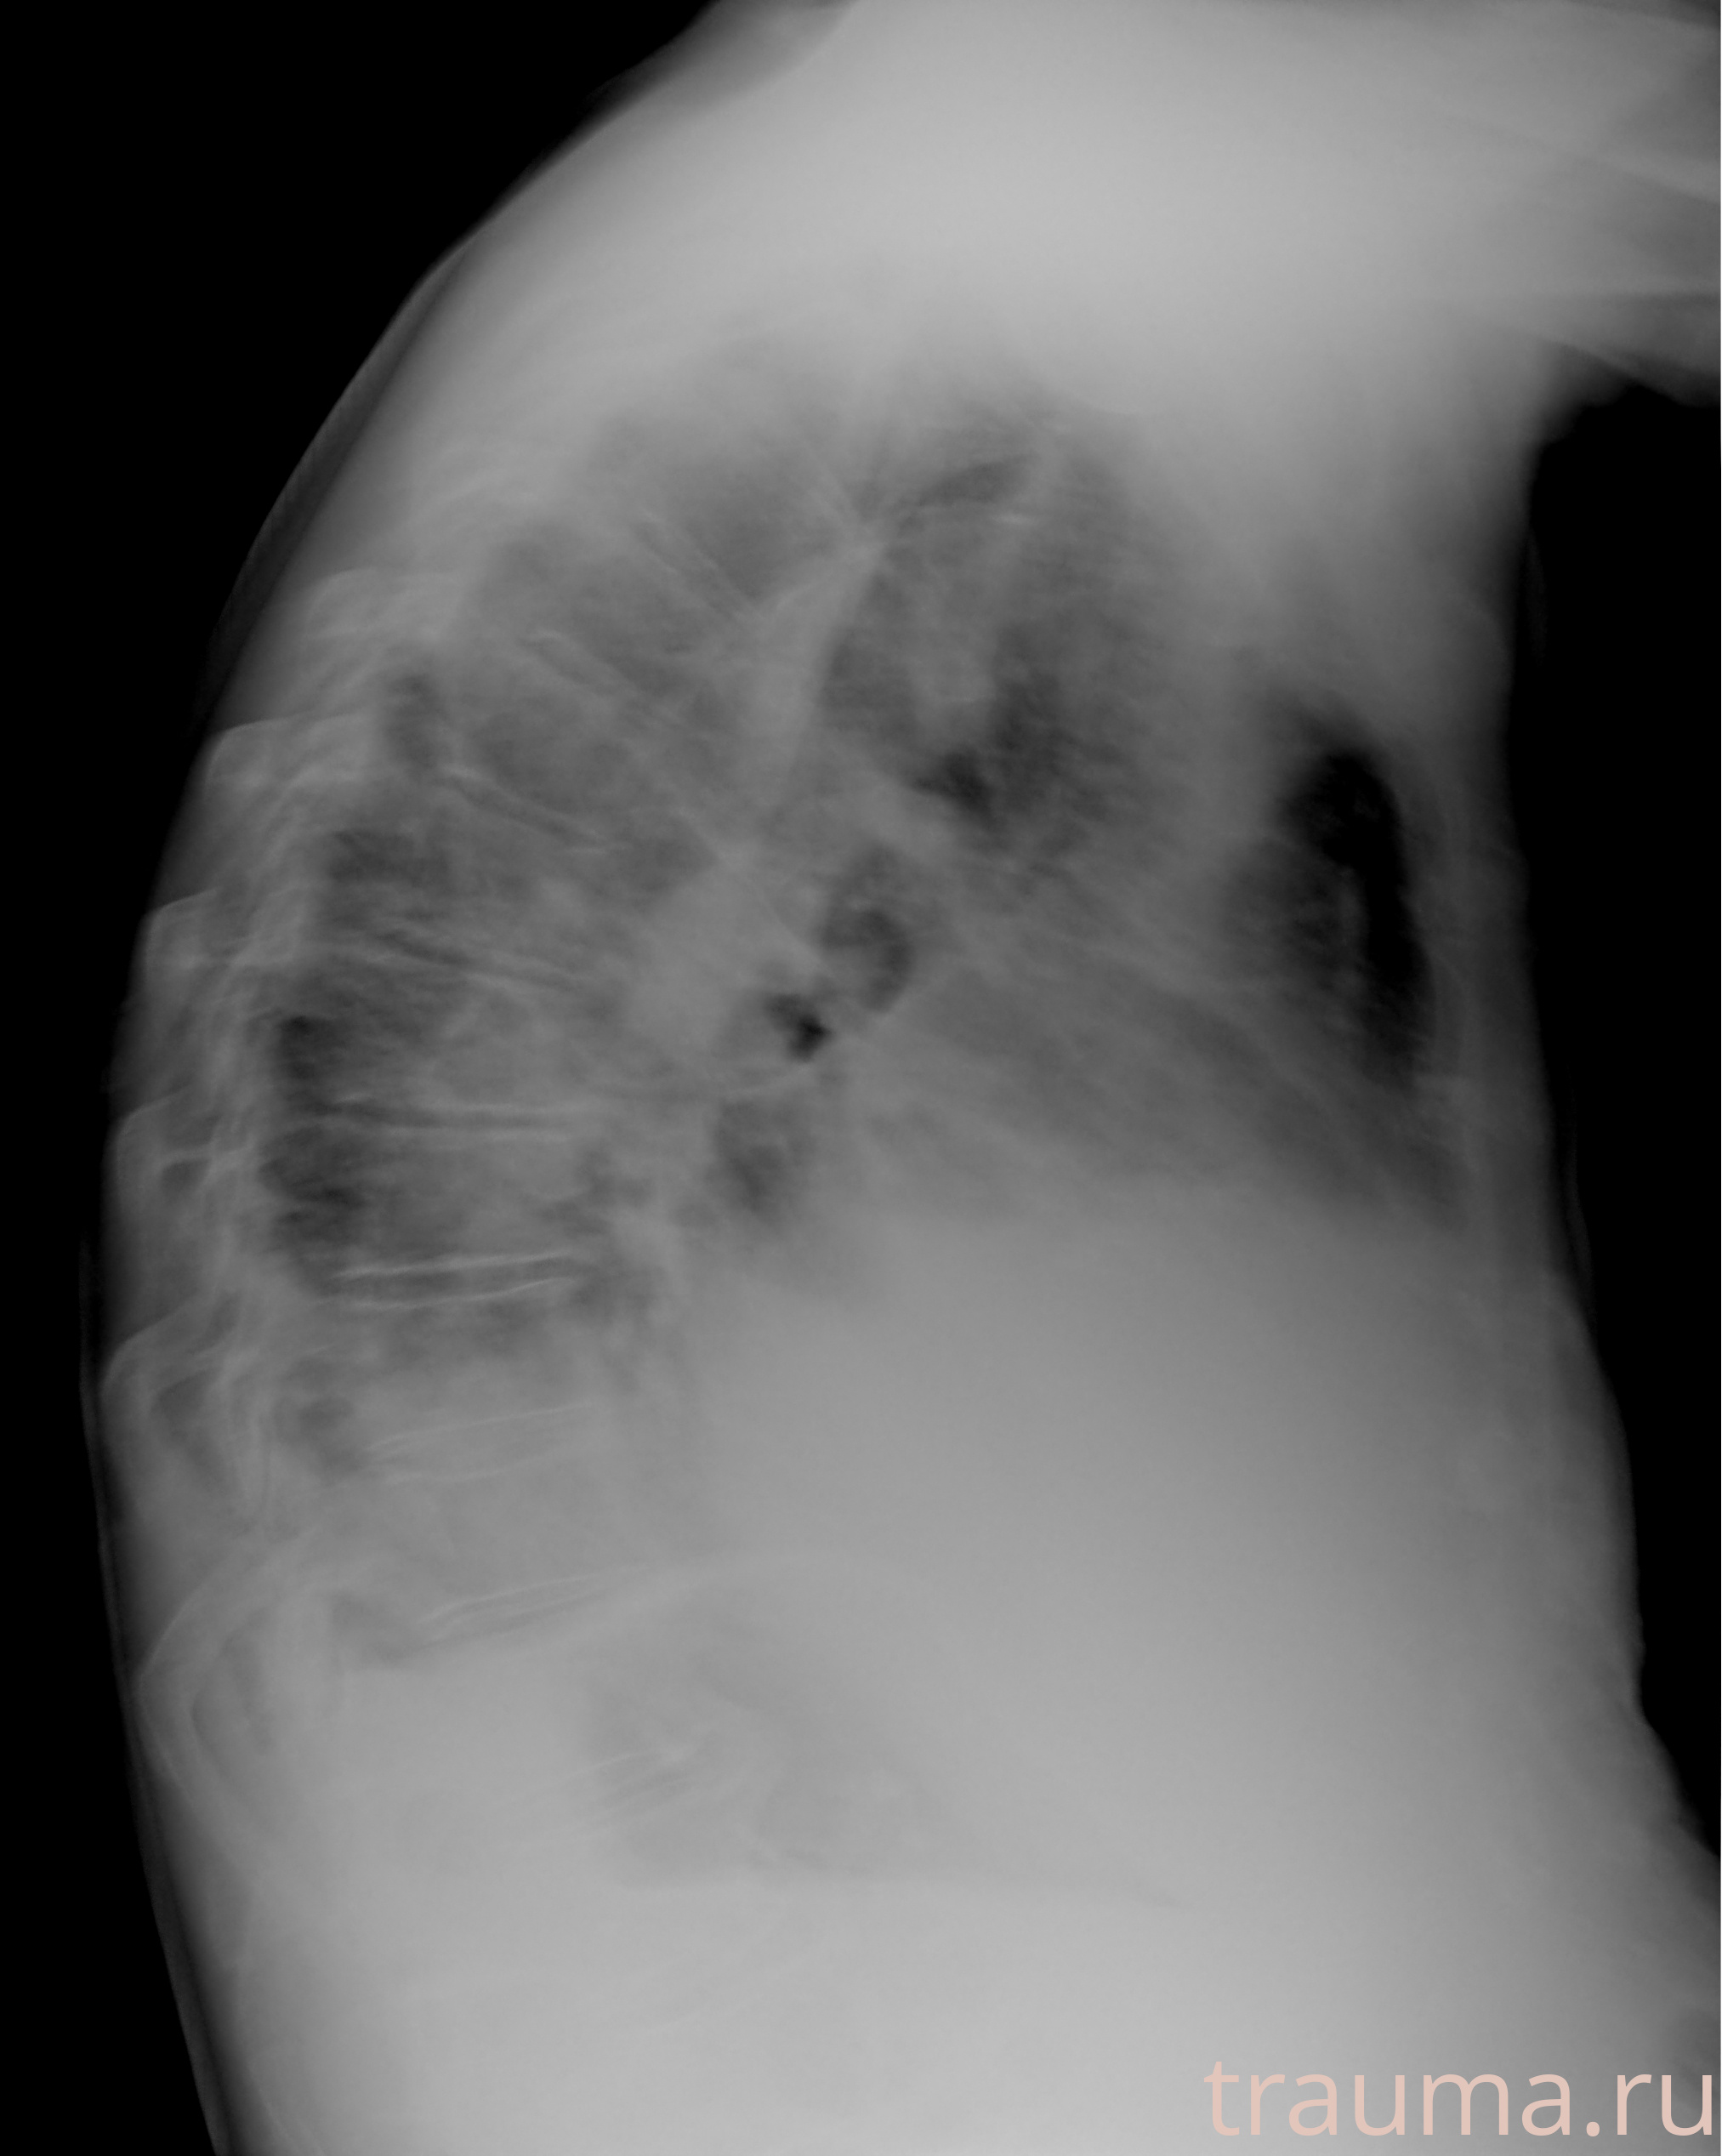

Рентген на дому: по вашему адресу приезжает врач-рентгенолог, травматолог-ортопед с мобильным рентгеновским аппаратом, проводит диагностику травмы или заболевания, делает необходимые рентгенограммы, дает рекомендации по дальнейшему лечению. Получить качественные снимки в домашних условиях возможно благодаря уникальной методике, разработанной МосРентген Центром для института  Склифосовского

при переломе шейки бедра и пневмонии от компании МосРентген Центр - партнера Института имени Склифосовского